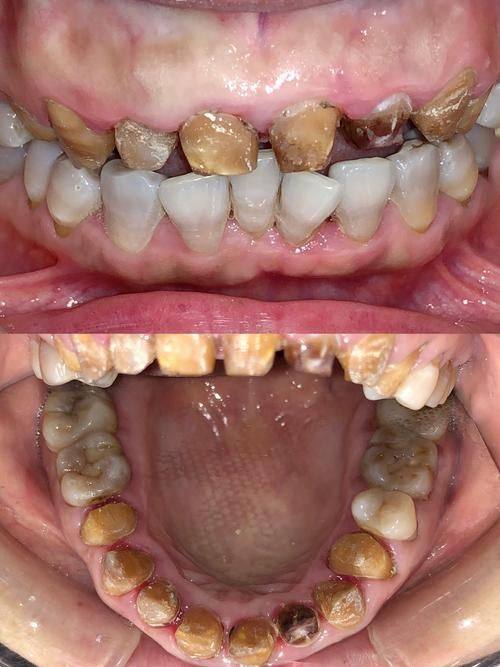

补牙:采用符合口腔生物相容性的补牙材料,针对龋齿、牙齿缺损等问题进行精细修复

儿牙治疗:针对儿童龋齿、乳牙早失等问题开展诊疗,同时注重儿童心理疏导,缓解看牙恐惧